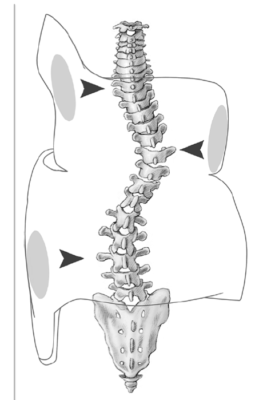

Vẹo cột sống là một biến dạng ba chiều của cột sống và thân mình, với các bất thường xảy ra ở:

- mặt phẳng trán – có sự dịch chuyển sang bên của thân mình trên xương chậu

- mặt phẳng đứng dọc – có một sự thay đổi trong cân bằng giữa các đường cong lõm/lồi

- mặt phẳng ngang – có sự xoay của đốt sống.

- Khi trẻ cúi xuống sẽ làm nổi phía sau (phía lồi của đường cong) một cái bướu do các xương sườn phần ngực phía lồi xoay ra sau theo đốt sống.

- Hai vai chênh nhau, không cân xứng (vai bị nhô lên ở phía lồi của đường cong).

- Bả vai nổi rõ và bị kéo nhẹ lên trên.

- Tay phía bị sát vào thân hơn tay kia.

- Lệch hông.

- Cột sống vùng thắt lưng bị ưỡn ra.